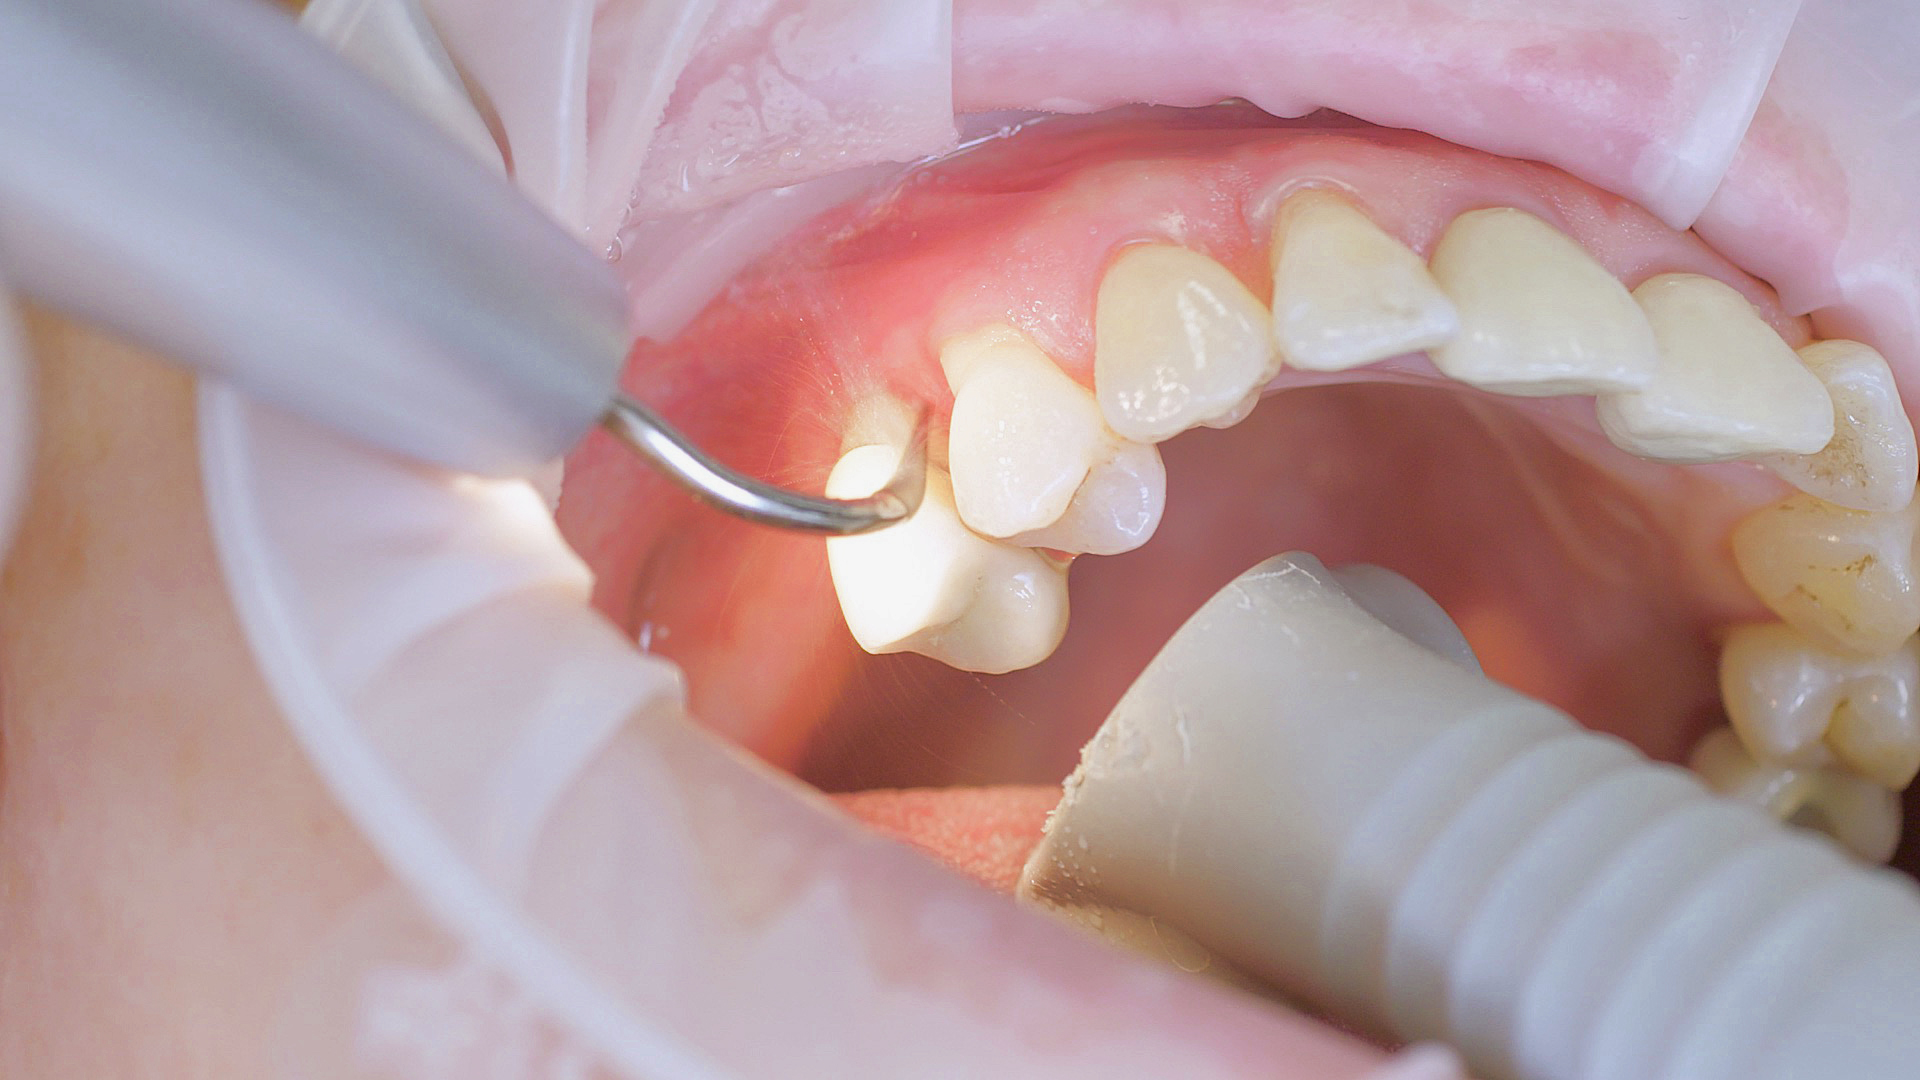

Si nécessaire, un traitement parodontal préventif est effectué. Un nettoyage dentaire professionnel contribue dans un premier temps à des conditions gingivales saines. Il permet d’éliminer le tartre (Fig. 1) et le biofilm (Fig. 2) jusque dans le sulcus gingival. En association à des consignes d’hygiène buccodentaire méticuleuses,

il élimine également à long terme le risque de récidives d'inflammation chez le patient.[15]